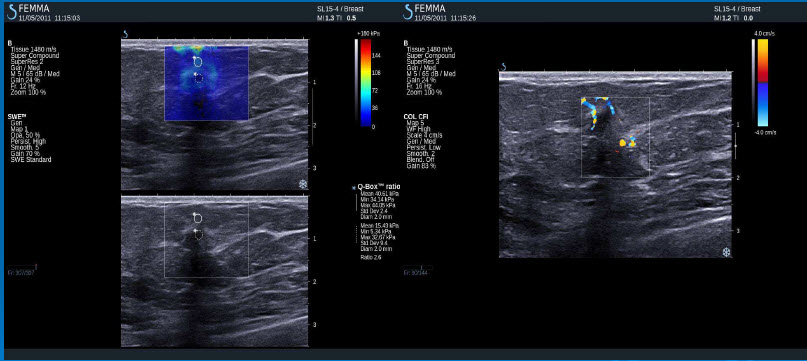

Cysty

Negativní výsledky elastografie / histologicky potvrzená malignita

DCIS